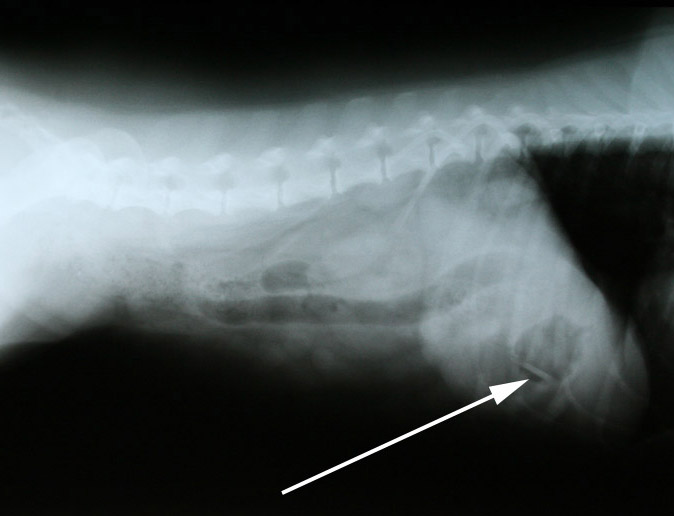

Omdat zo’n vreemd voorwerp zeker wel de oorzaak van de klachten van Fanny zou kunnen zijn en het chronisch braken een reden is voor verder onderzoek, hebben we röntgenfoto’s gemaakt.

en op de andere foto’s wel: